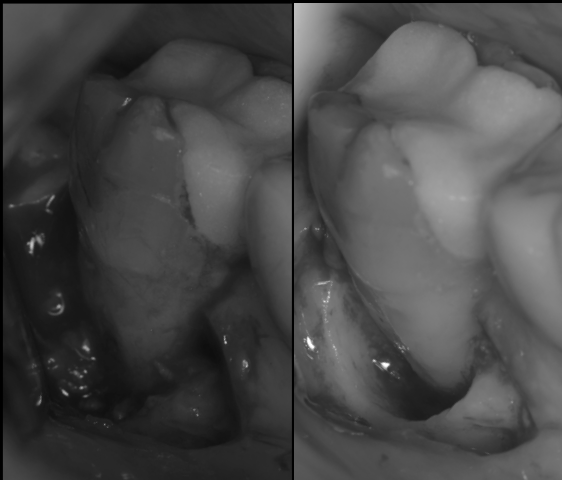

治療前

治療後

池袋院での症例紹介

グランドメゾンデンタルクリニックでは、歯周病専門医がマイクロスコープと歯科用CTを駆使し、根分岐部病変への適切な診断・治療を行っています。